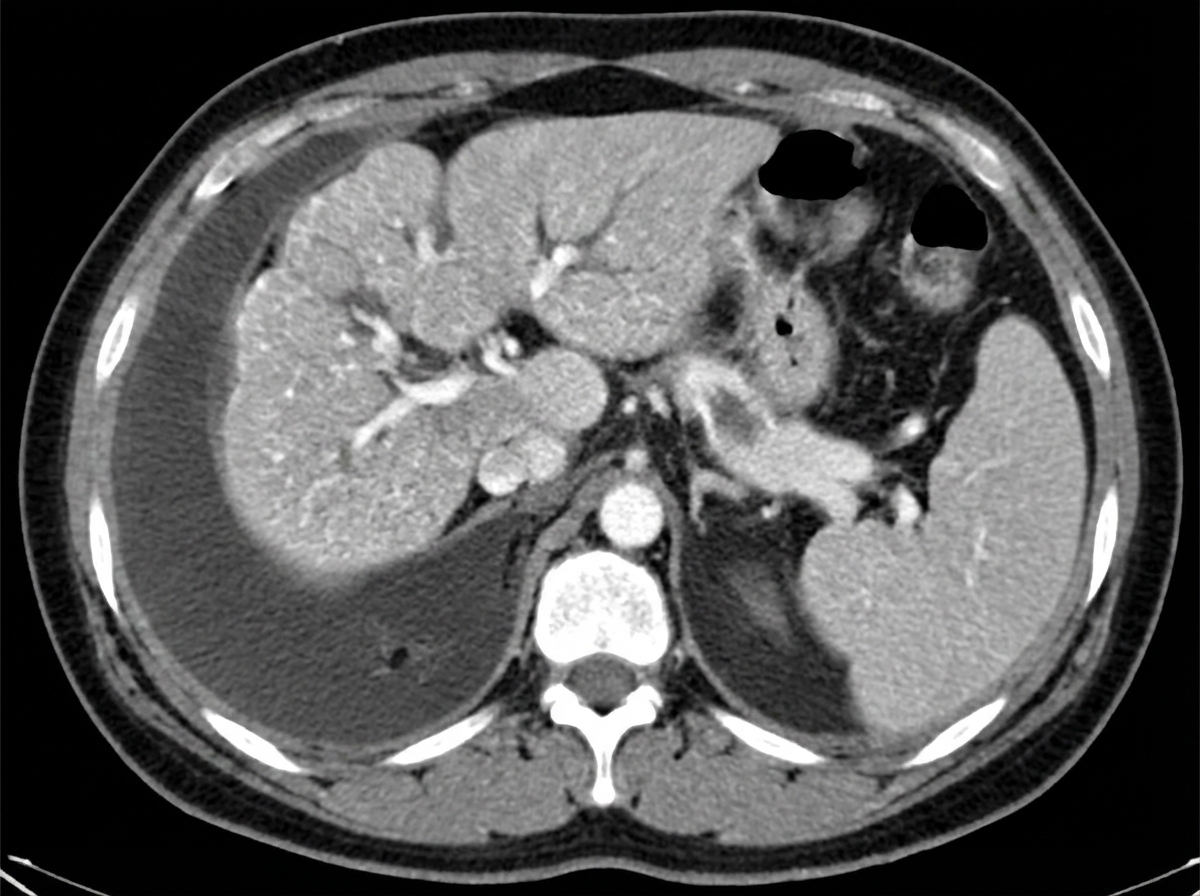

A 65-year-old man is brought to the emergency department because of a 1-day history of fever and disorientation. His wife reports that he had abdominal pain and diarrhea the previous day. He drinks 60 oz of alcohol weekly. His pulse is 110/min and blood pressure is 96/58 mm Hg. Examination shows jaundice, palmar erythema, spider nevi on his chest, dilated veins on the anterior abdominal wall, and 2+ edema of the lower extremities. The abdomen is soft and diffusely tender; there is shifting dullness to percussion. His albumin is 1.4 g/dL, bilirubin is 5 mg/dL, and prothrombin time is 31 seconds (INR = 3.3). Hepatitis serology is negative. A CT scan of the abdomen is shown. Which of the following processes is the most likely explanation for these findings?

Explanation: ***Fibrous bands surrounding regenerating hepatocytes*** - The patient presents with classic signs of **cirrhosis** (jaundice, palmar erythema, spider nevi, dilated abdominal veins, edema, ascites), acute decompensation (fever, disorientation, hypotension), and severe **hepatic dysfunction** (low albumin, high bilirubin, prolonged PT/INR). The history of heavy alcohol use supports this. - **Cirrhosis** is histologically characterized by diffuse **fibrosis** and the formation of **regenerative nodules**, which are hepatocytes surrounded by fibrous bands, leading to disruption of normal liver architecture and function. *Accumulation of iron in hepatocytes* - This is characteristic of **hereditary hemochromatosis**, which leads to **iron overload** and organ damage, including cirrhosis. - While hemochromatosis can cause cirrhosis, the patient's acute symptoms and specific liver histology (macronodular cirrhosis often seen in alcoholic liver disease) make alcoholic cirrhosis a more direct fit, and there is no mention of increased iron in labs. *Ground-glass hepatocytes with cytotoxic T cells* - **Ground-glass hepatocytes** are typically seen in **chronic hepatitis B infection**, representing an accumulation of HBsAg in the endoplasmic reticulum. - While chronic hepatitis B can lead to cirrhosis, the negative hepatitis serology and direct evidence of alcohol abuse do not support this as the primary cause. *Misfolded protein aggregates in hepatocellular endoplasmic reticulum* - This description is characteristic of **alpha-1 antitrypsin deficiency**, where defective alpha-1 antitrypsin accumulates in hepatocytes. - Although it can cause cirrhosis, the patient's symptoms are more consistent with alcoholic liver disease, and there is no mention of respiratory symptoms often associated with alpha-1 antitrypsin deficiency. *Hepatocyte swelling with Councilman bodies and monocyte infiltration* - **Hepatocyte swelling** and **Councilman bodies** (apoptotic hepatocytes) are features of **acute viral hepatitis** or other forms of acute liver injury. Monocyte infiltration can also occur. - While acute liver injury can occur, the chronic stigmata of liver disease (spider nevi, palmar erythema, ascites) and the history of alcohol abuse point to a chronic process like cirrhosis rather than just acute inflammation.